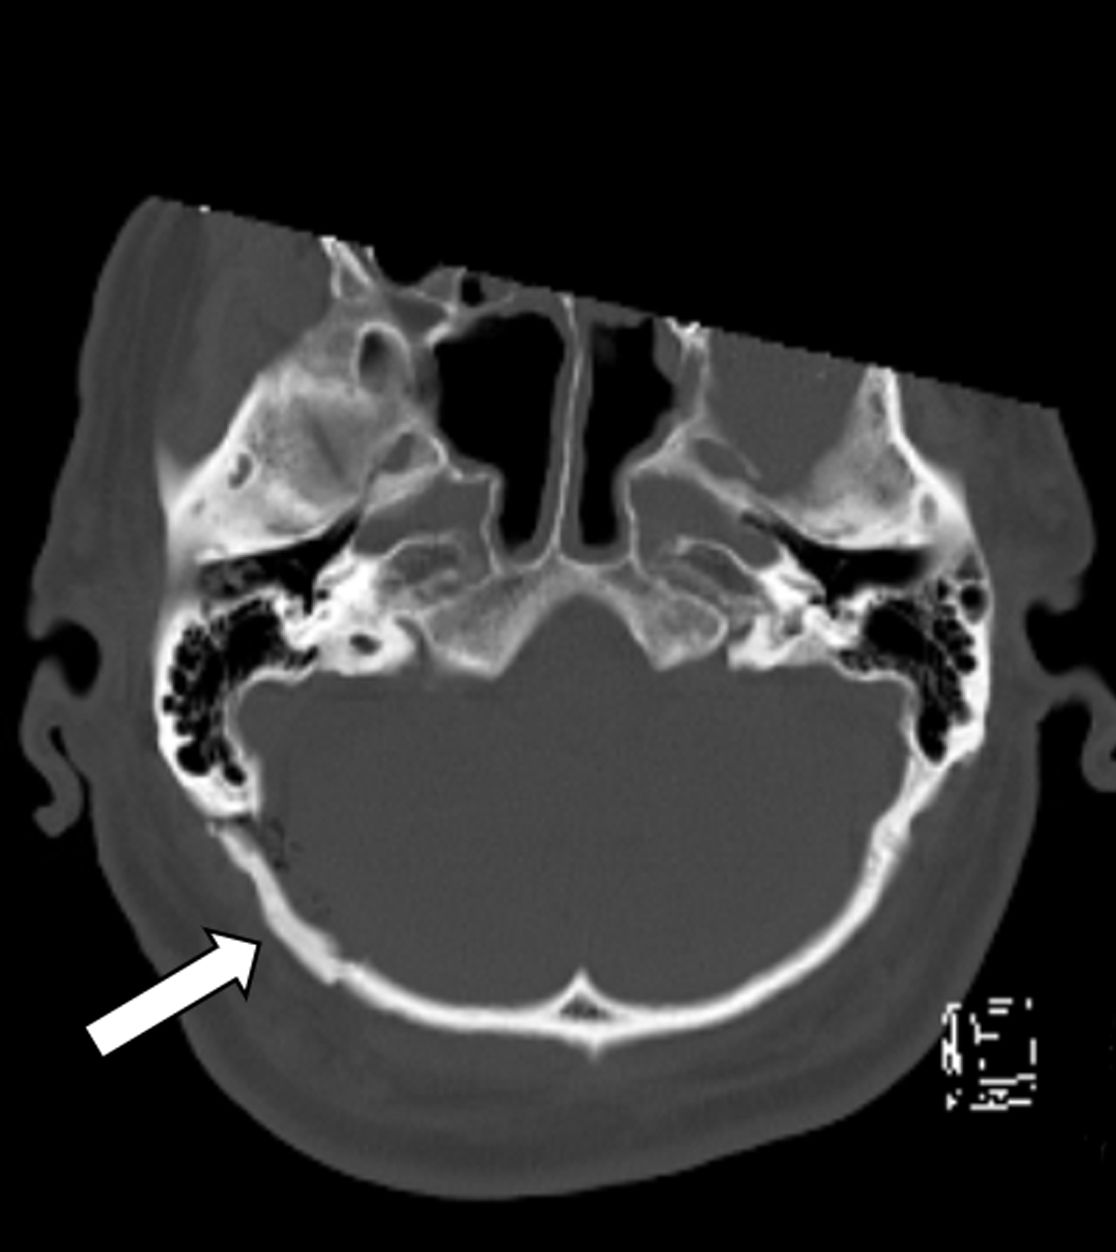

Gefäß-Nerven-Kontakt im Bereich des Nervus trigeminus (Pfeil)

Status nach mikrovaskulärer Dekompression über einen Zugang hinter dem Ohr (Pfeil)